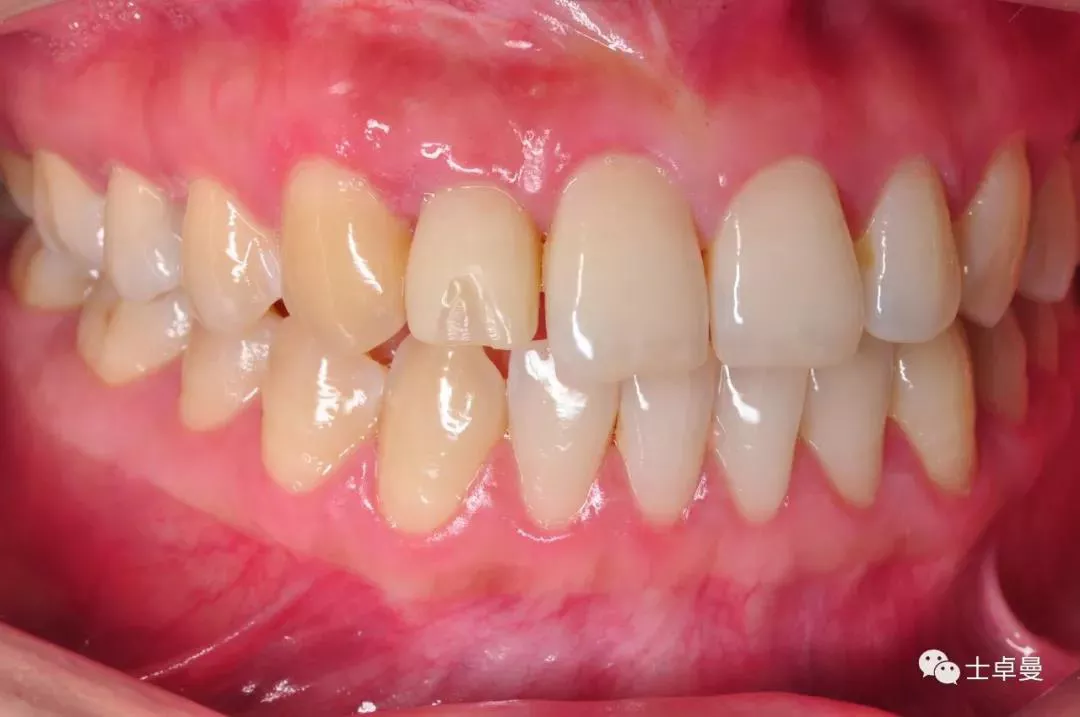

完成修复一年后复查

修复后3年复查

患者微笑照